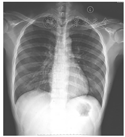

7月12日床旁胸部X线片(图3)示病灶好转吸收,完善风湿三项、免疫六项、自免十二项、结核抗体、抗中性粒细胞胞质抗体、磷脂综合征二项以及G试验,结果回报均阴性。至7月14日患者情况保持稳定,甲泼尼龙琥珀酸钠予逐渐减量,改为80 mg静脉滴注,每8 h 1次,并复查骨髓检查。7月15日床边胸片示病灶继续吸收,停无创呼吸机后复查血气仍提示Ⅰ型呼吸衰竭,深部痰培养出产超广谱β内酰胺酶的肺炎克雷伯菌(亚胺培南敏感),改亚胺培南西司他丁钠、伏立康唑维持,骨髓涂片报告当日回复:骨髓增生减低,G=41%,E=1.5%,G/E=27.67∶1。粒系增生减低,可见约7.5%原始、早幼粒细胞,破碎细胞易见,提示疾病未缓解,予亚砷酸10 mg静脉滴注,每日1次,继续诱导分化。7月18日情况稳定,甲泼尼龙琥珀酸钠继续减量,改为80 mg静脉滴注每日2次,其后每3~4天予减量1次,减至10 mg后维持至出院后。7月22日血常规:白细胞计数1.92 × 109/L,中性粒细胞计数1.56 × 109/L,血红蛋白83 g/L,血小板计数91 × 109/L,粒细胞缺乏恢复,情况稳定,停无创呼吸机。8月12日(亚砷酸治疗第29天)复查骨髓:骨髓涂片:骨髓增生活跃,粒系增生活跃,见个别早幼粒细胞,分叶略多于杆状核粒细胞。PML-RARα融合基因拷贝数<20,PML-RARα/ABL1<0.001。免疫残留:原始-前体细胞约占有核细胞的0.5%,CD34+细胞约占0.09%,未见免疫表型明显异常的细胞。评价疾病完全缓解。改甲泼尼龙10 mg每日1次口服维持治疗。8月11日复查胸部CT炎性反应基本吸收(图4),患者情况稳定于8月16日出院。8月22日复查胸部X线片(图5)心肺均未见病变,无呼吸系统后遗症,停甲泼尼龙。定期返院序贯诊疗,疾病均未复发,至今生存。